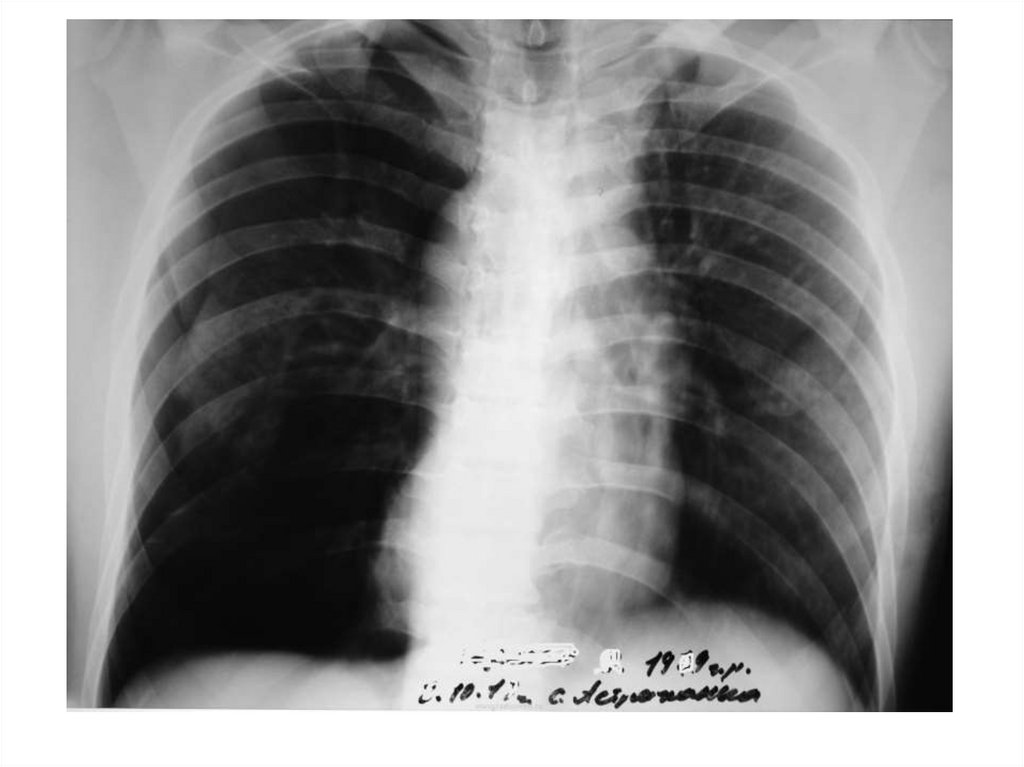

13. Уменьшение притока крови

Причина - гиповолемия малого круга

кровообращения при некоторых врожденных

пороках сердца (тетрада Фалло,

изолированный стеноз легочной артерии).

Видимая картина – двустороннее тотальное

просветление над всеми легочными полями.

14.

Гипоплазия

левой ветви

легочной

артерии

15. Наличие воздуха в плевральной полости